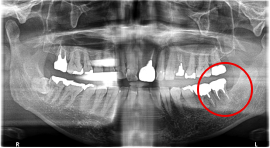

Before

※赤丸を抜歯しました。

After